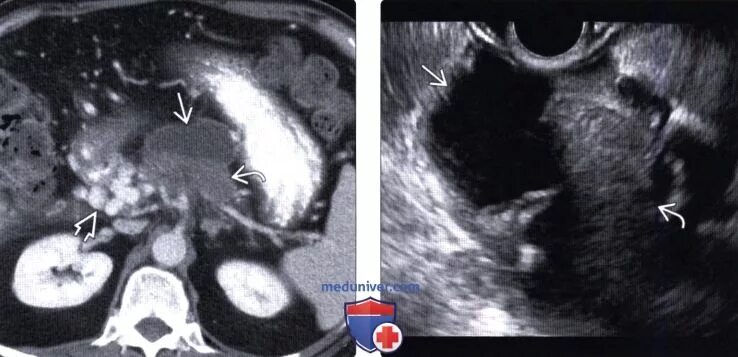

Мрт кисты поджелудочной